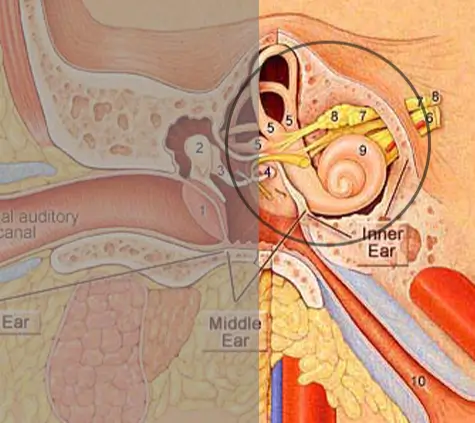

- Signals are sent to the brain via the auditory nerve

Sensorineural hearing loss happens due to damage in the inner ear (cochlea) or the auditory nerve pathways that carry sound to the brain.

It is usually permanent and the most common type of hearing loss. Causes include aging, loud noise exposure, genetics, medications, or conditions like Meniere’s disease

For individuals with severe to profound SNHL, cochlear implants bypass the damaged part of the ear, directly stimulating the auditory nerve